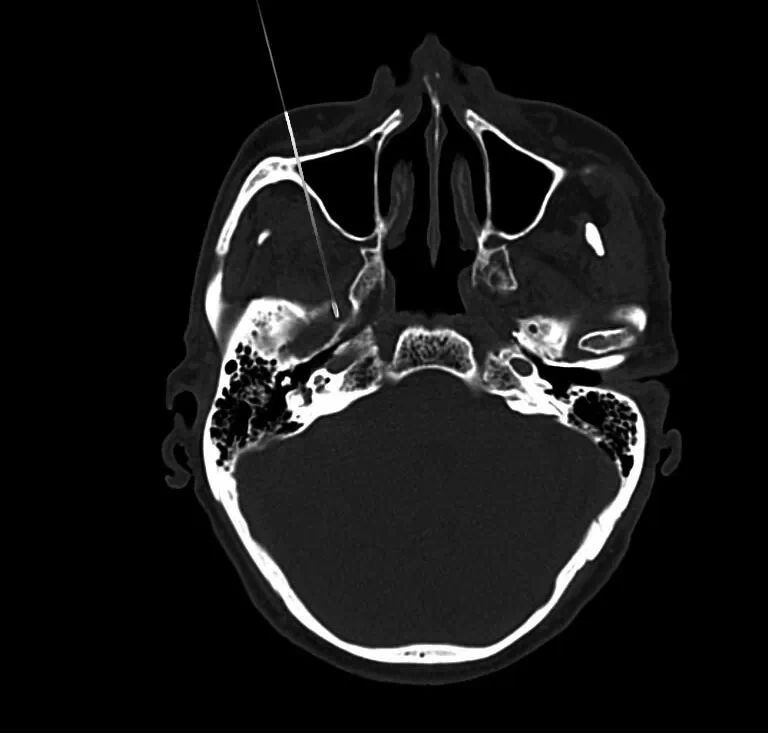

四川奥斯迪康骨医院治疗方法:CT引导射频热凝术

治疗原理:三叉神经为感觉神经,其中神经纤维(AA纤维和AB纤维)能耐受较高温度,而痛觉神经纤维不能耐高温,CT引导三叉神经热凝术选择破坏痛觉纤维,使患者疼痛治愈。